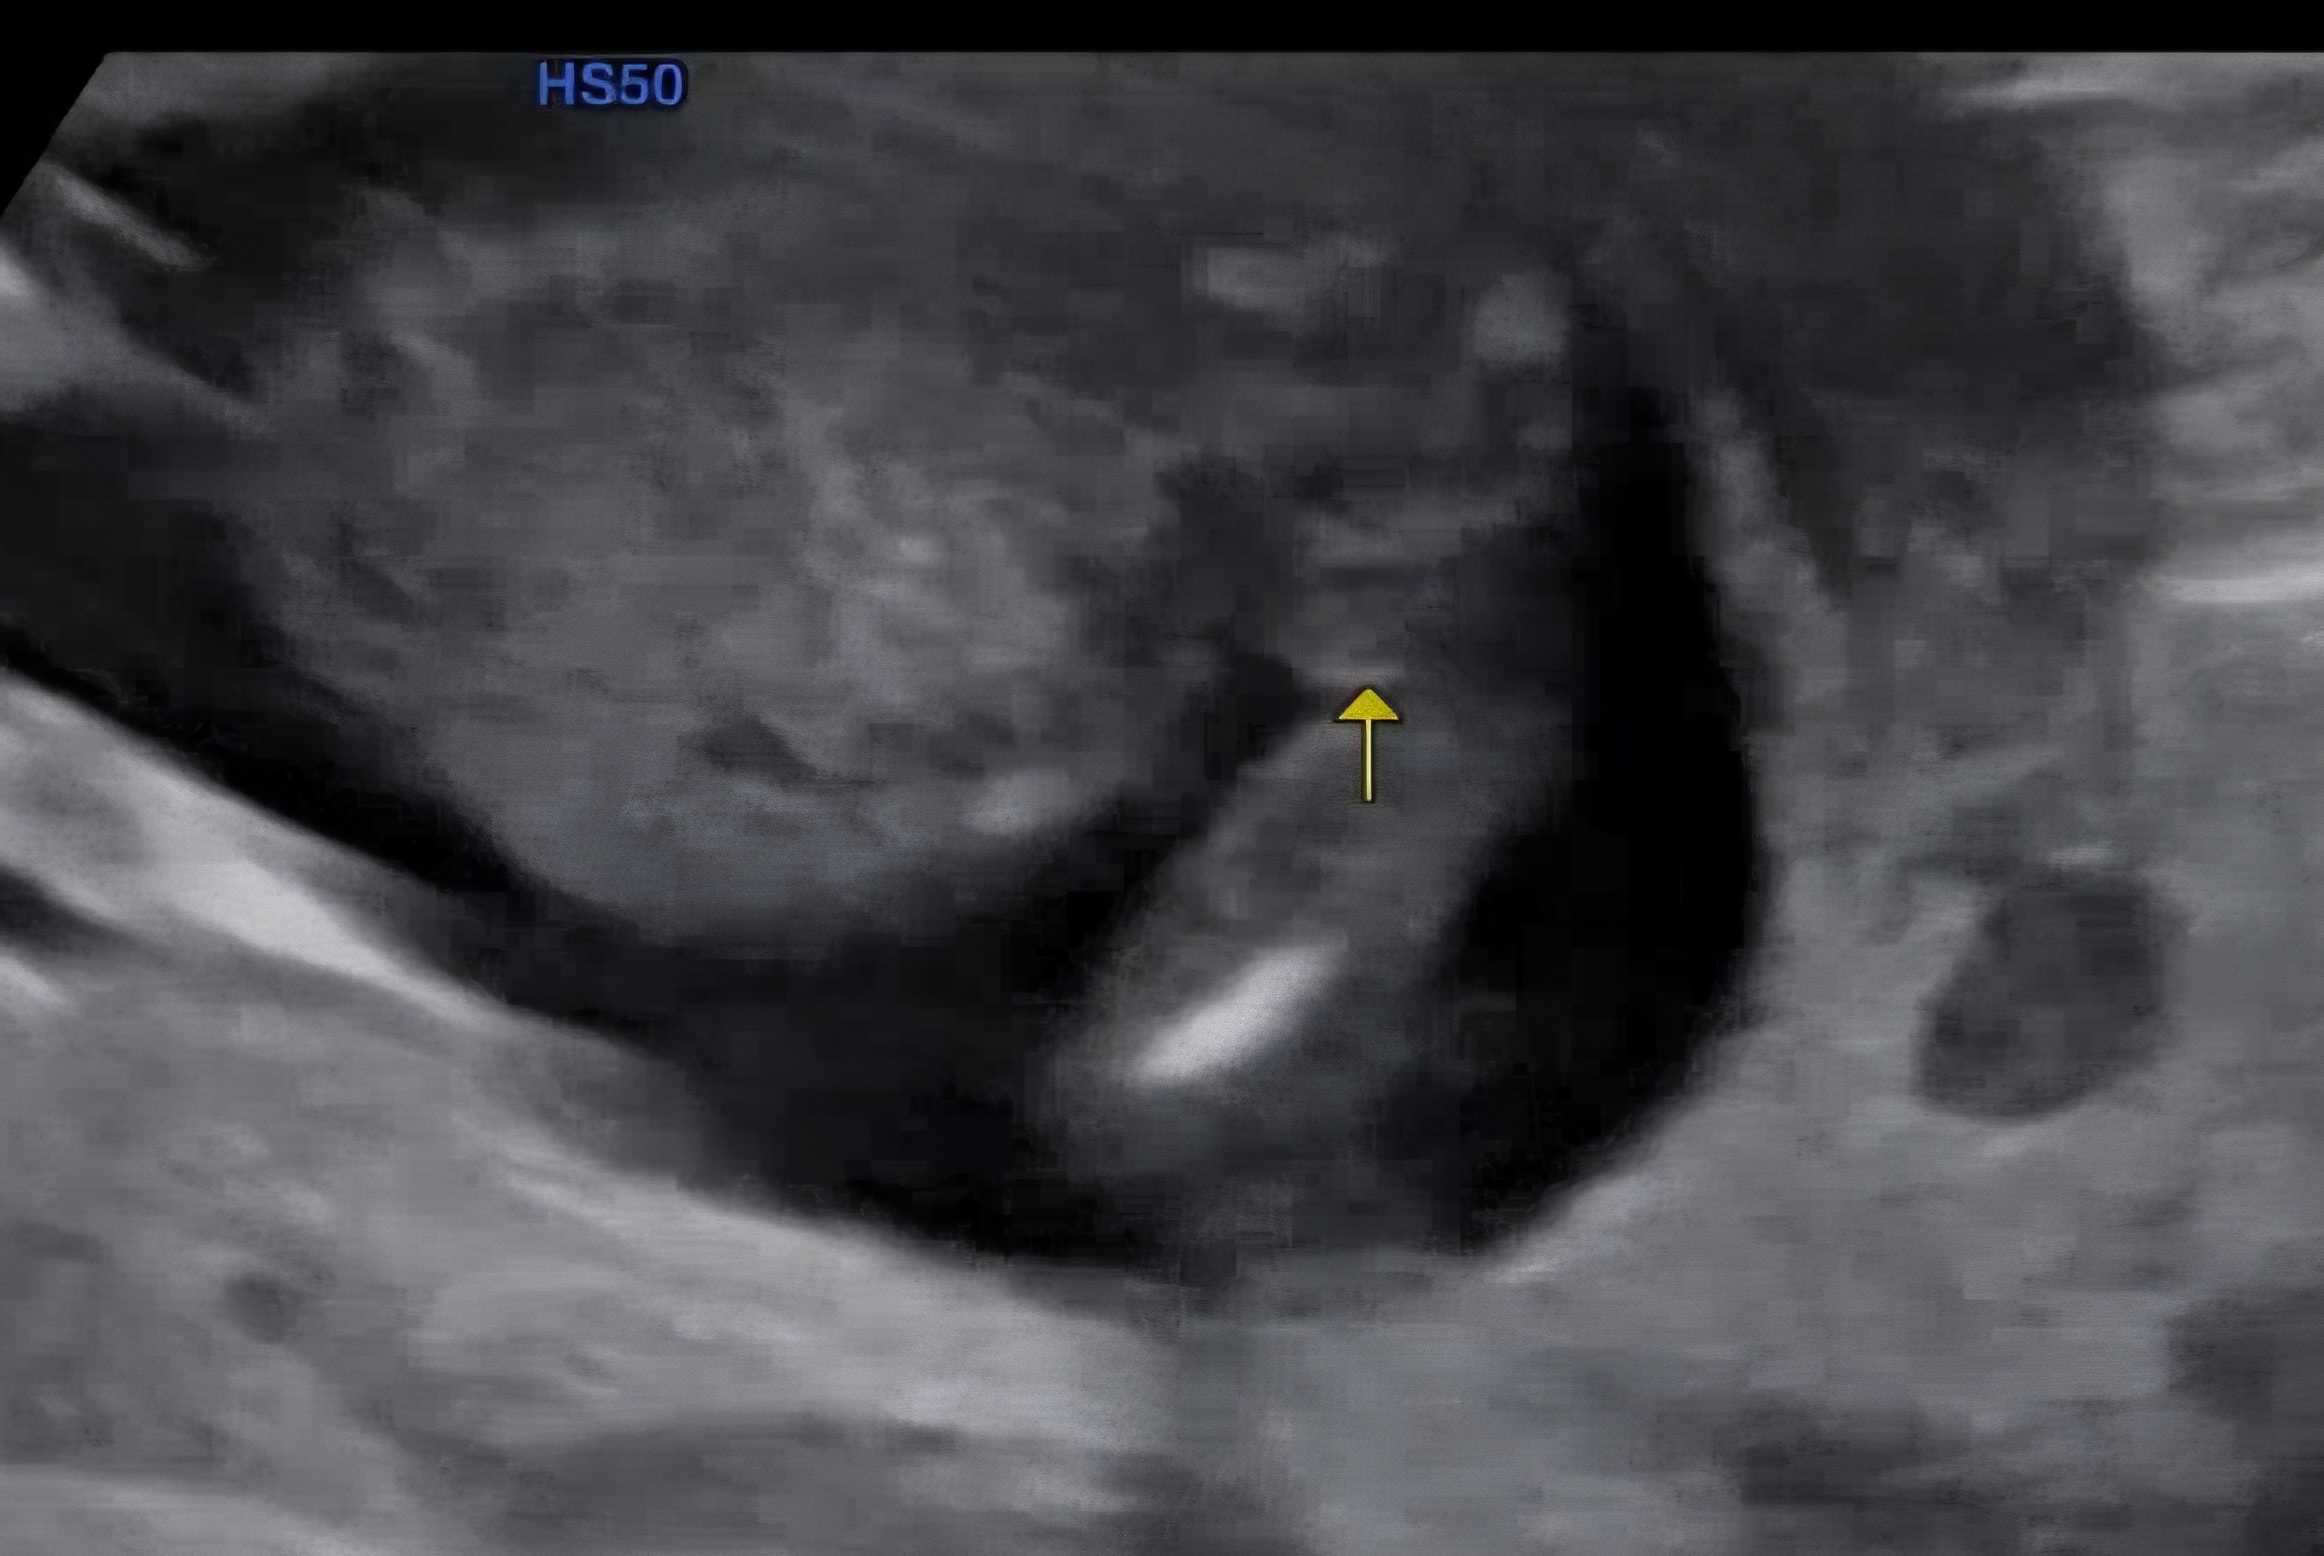

15주2일 촘파사진인데요!

아들의견많이 주셨었는데, 반전없이 아들로 생각하면 될까요?!!😅😅😅😅😅